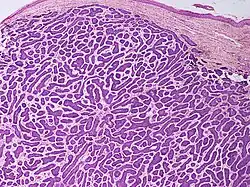

.jpg)

Nodular basal-cell carcinoma (also known as "classic basal-cell carcinoma") accounts for 50% of all BCC.[29] It most commonly occurs on the sun-exposed areas of the head and neck.[30]: 748 [31]: 646 Histopathology shows aggregates of basaloid cells with well-defined borders, showing a peripheral palisading of cells and one or more typical clefts.[29] Such clefts are caused by shrinkage of mucin during tissue fixation and staining.[32] Central necrosis with eosinophilic, granular features may also be present, as well as mucin. The heavy aggregates of mucin determine a cystic structure. Calcification may also be present, especially in long-standing lesions.[29] Mitotic activity is usually not so evident, but a high mitotic rate may be present in more aggressive lesions.[29] Adenoidal BCC can be classified as a variant of NBCC, characterized by basaloid cells with a reticulated configuration extending into the dermis.[29]